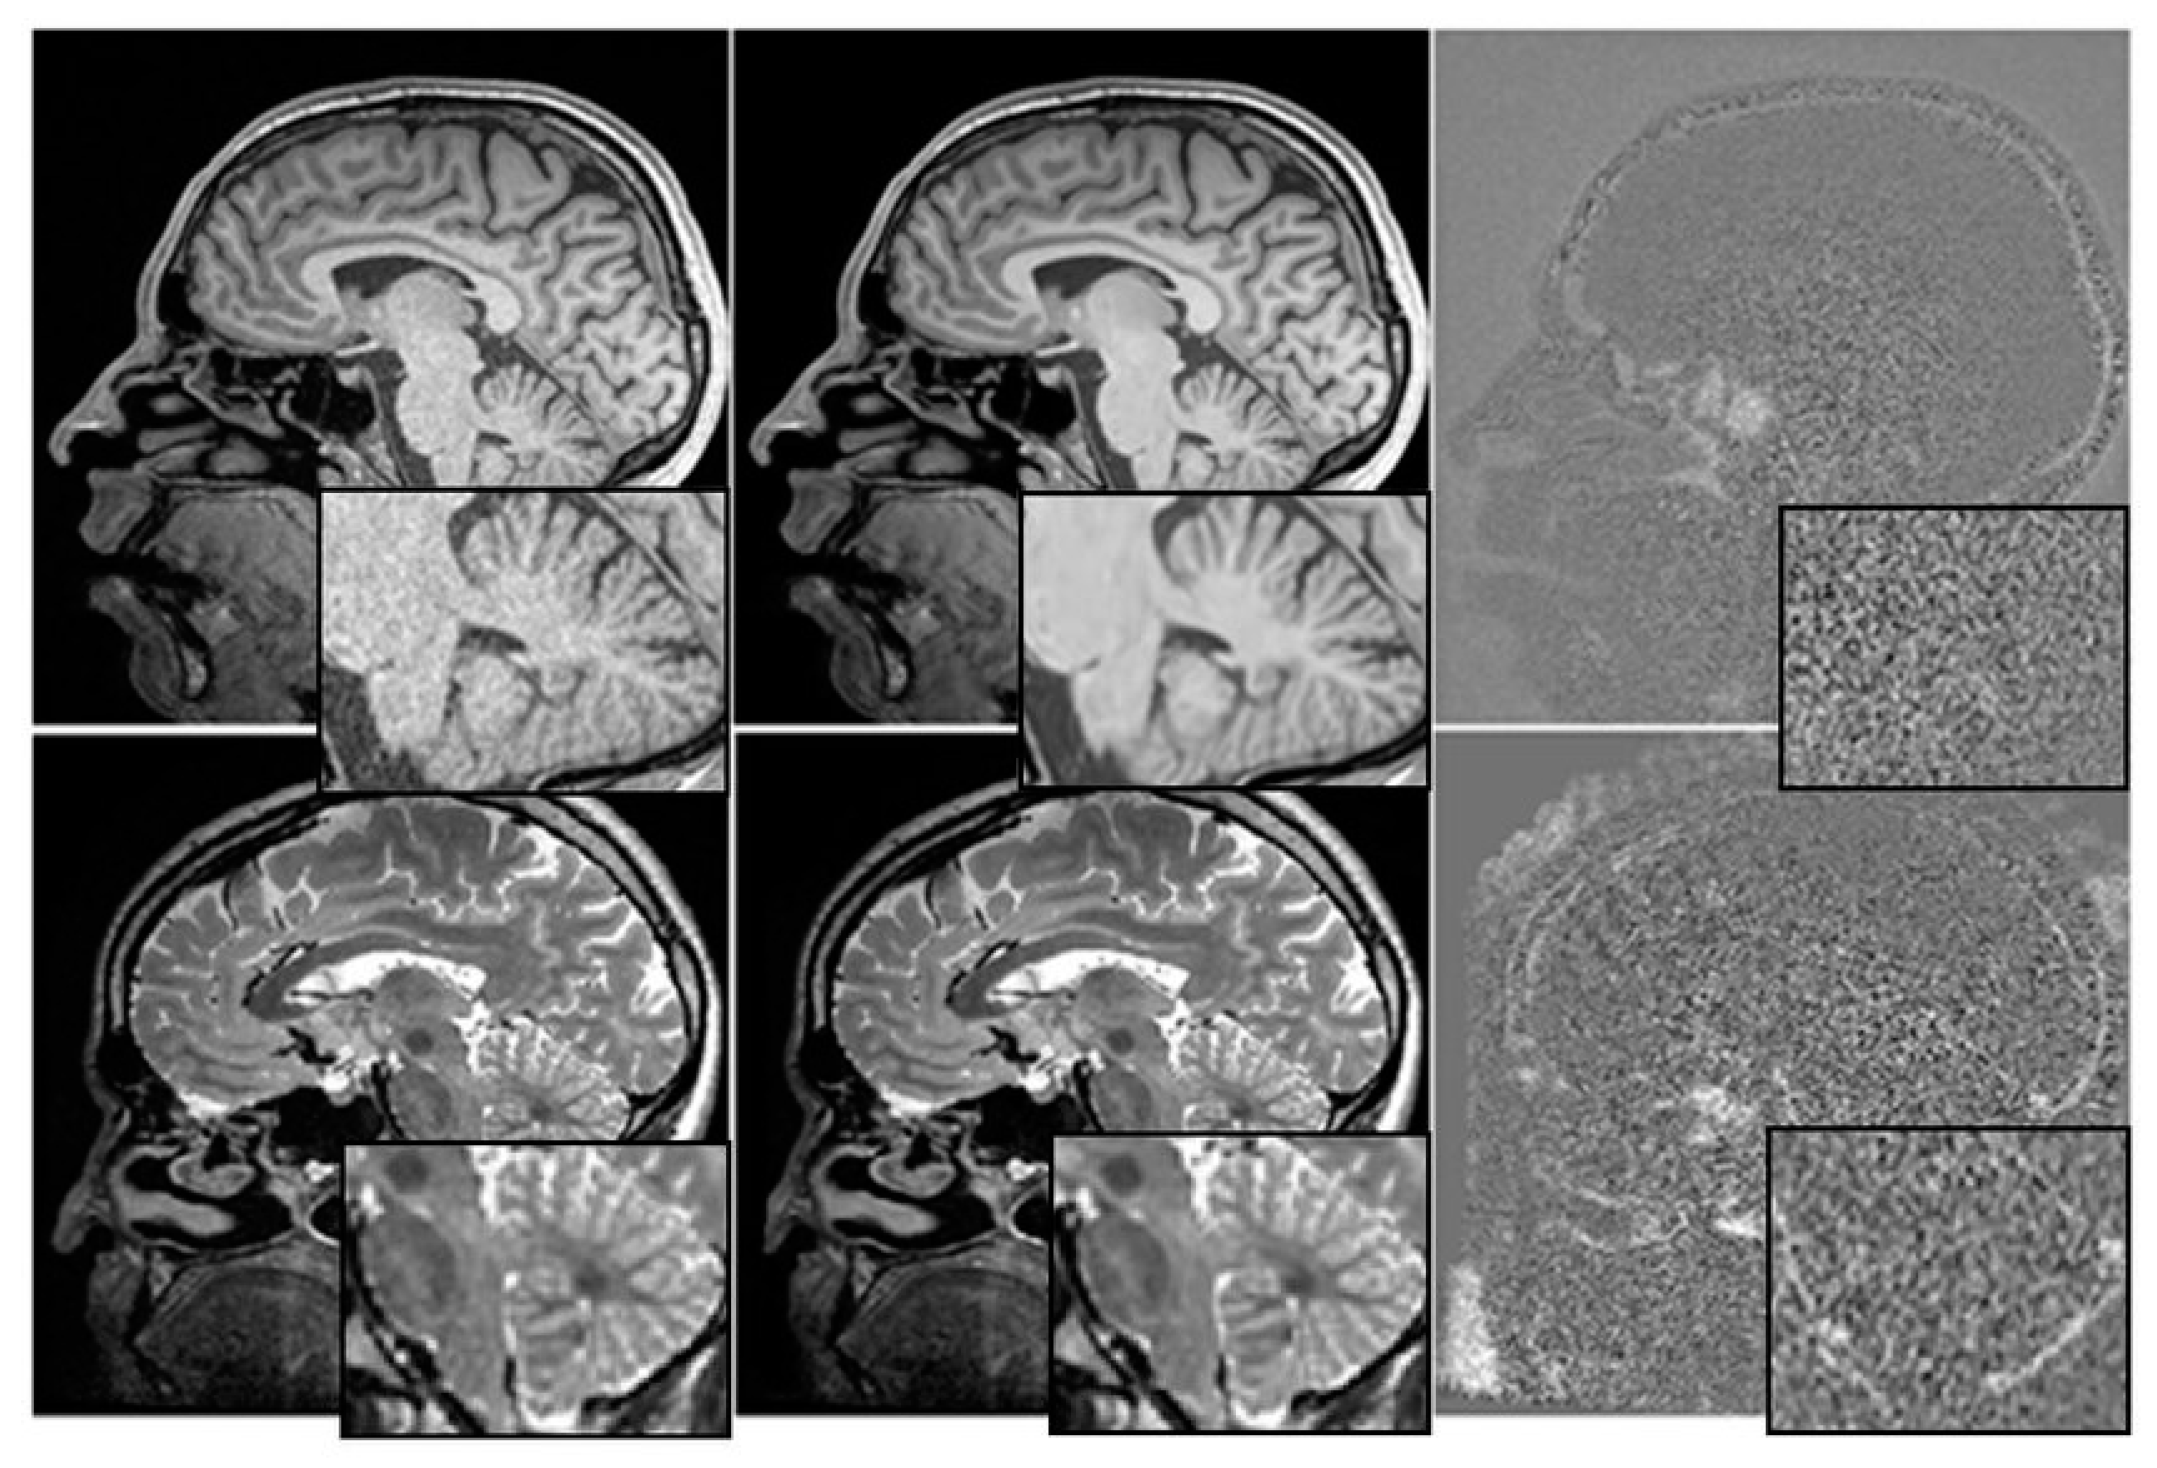

The relationship between cognitive tests, medication, and mental health is depicted graphically in Figure 3. We have investigated the utility of multimodal time-series data in making prognoses about the course of AD.

Figure 3.

Before and After Denoising.

Each patient is represented by four rows in each of the four time-series representations, with each row containing information from a single visit. The ADNI compiles attendance statistics once every six months. Researchers on the ADNI project gathered massive amounts of information over the course of more than a decade.

We have used T1-weighted MRI images acquired from a cohort of 100 patients diagnosed with AD and 100 age-matched healthy controls. The MRI images having a resolution of 1 mm × 1 mm × 1 mm and dimensions of 256 × 256 × 160. The intensity values of each pixel in the MRI images ranged from 0 to 255.

Before training the Mayfly optimization algorithm, the MRI images were pre-processed by applying skull stripping, intensity normalization, and spatial normalization using the SPM12 toolbox. The images segmented into grey matter, white matter, and cerebrospinal fluid using the FSL software.

To train the algorithm, leave-one-out cross-validation approach has been used where one patient was left out for testing, and the remaining 199 patients for training. The input to the algorithm consisted of the segmented grey matter images, which were resized to 128 × 128 × 80 to reduce the computational burden.

By providing this level of detail about the input data, the authors can help readers better understand the characteristics of the MRI images used in the study and how they may have influenced the results. This information can also be useful for other researchers who want to reproduce the study or compare it with other studies that use similar input data.